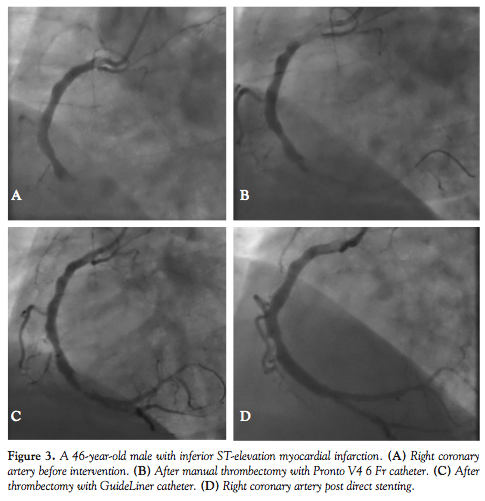

Between December 2011 and May 2013, a total of 17 patients presenting with ACS (12 ST-elevation myocardial infarction [STEMI] and 5 non-ST elevation myocardial infarction [NSTEMI]) involving 18 culprit vessels were treated specifically for manual thrombus aspiration utilizing the guide extension catheter, wherein severe thrombus burden was identified (Table 2). This included 9 right coronary artery (RCA) interventions (Figure 1), 4 saphenous vein graft (SVG) interventions (Figure 2), 2 left anterior descending (LAD) artery interventions, 2 left circumflex (LCX) coronary artery interventions, and 1 ramus intermedius (RI) artery intervention. Four culprit native vessel lesions were the result of late thrombosis within previously placed stents. A 6 Fr Launcher guide catheter was utilized in all cases of manual aspiration with the GuideLiner V2 catheter as the mother-and-child aspiration system. Drug-eluting stents were deployed in all but 1 case post aspiration,

using the direct stenting technique.

Successful outcomes as judged by symptom resolution, improvement in ST-segments, and obtaining brisk Thrombolysis in Myocardial Infarction (TIMI)-3 flow occurred in 17/18 vessels treated. Myocardial blush grade (MBG) of 2 or greater was achieved in 94.4% of patients undergoing PCI with manual aspiration (Table 3). A single case of an acutely occluded SVG that was thrombus laden proximal to distal had an unsuccessful outcome. Initial aspiration with the Pronto catheter in 3 cases and the Export catheter in 1 case was unsuccessful (Figure 3B). Subsequent use of the guide extension catheter provided a successful outcome with thrombus aspiration (Figures 3C and 3D). In 1 case involving the LCX artery, delivery of the GuideLiner to the lesion was unsuccessful and aspiration was performed proximal to the lesion with direct stenting of the lesion with a successful outcome noted both clinically and by angiography.